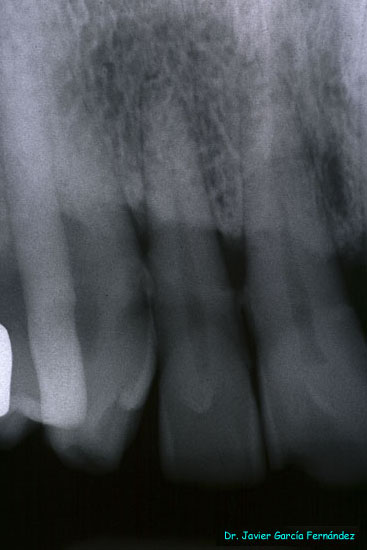

image029